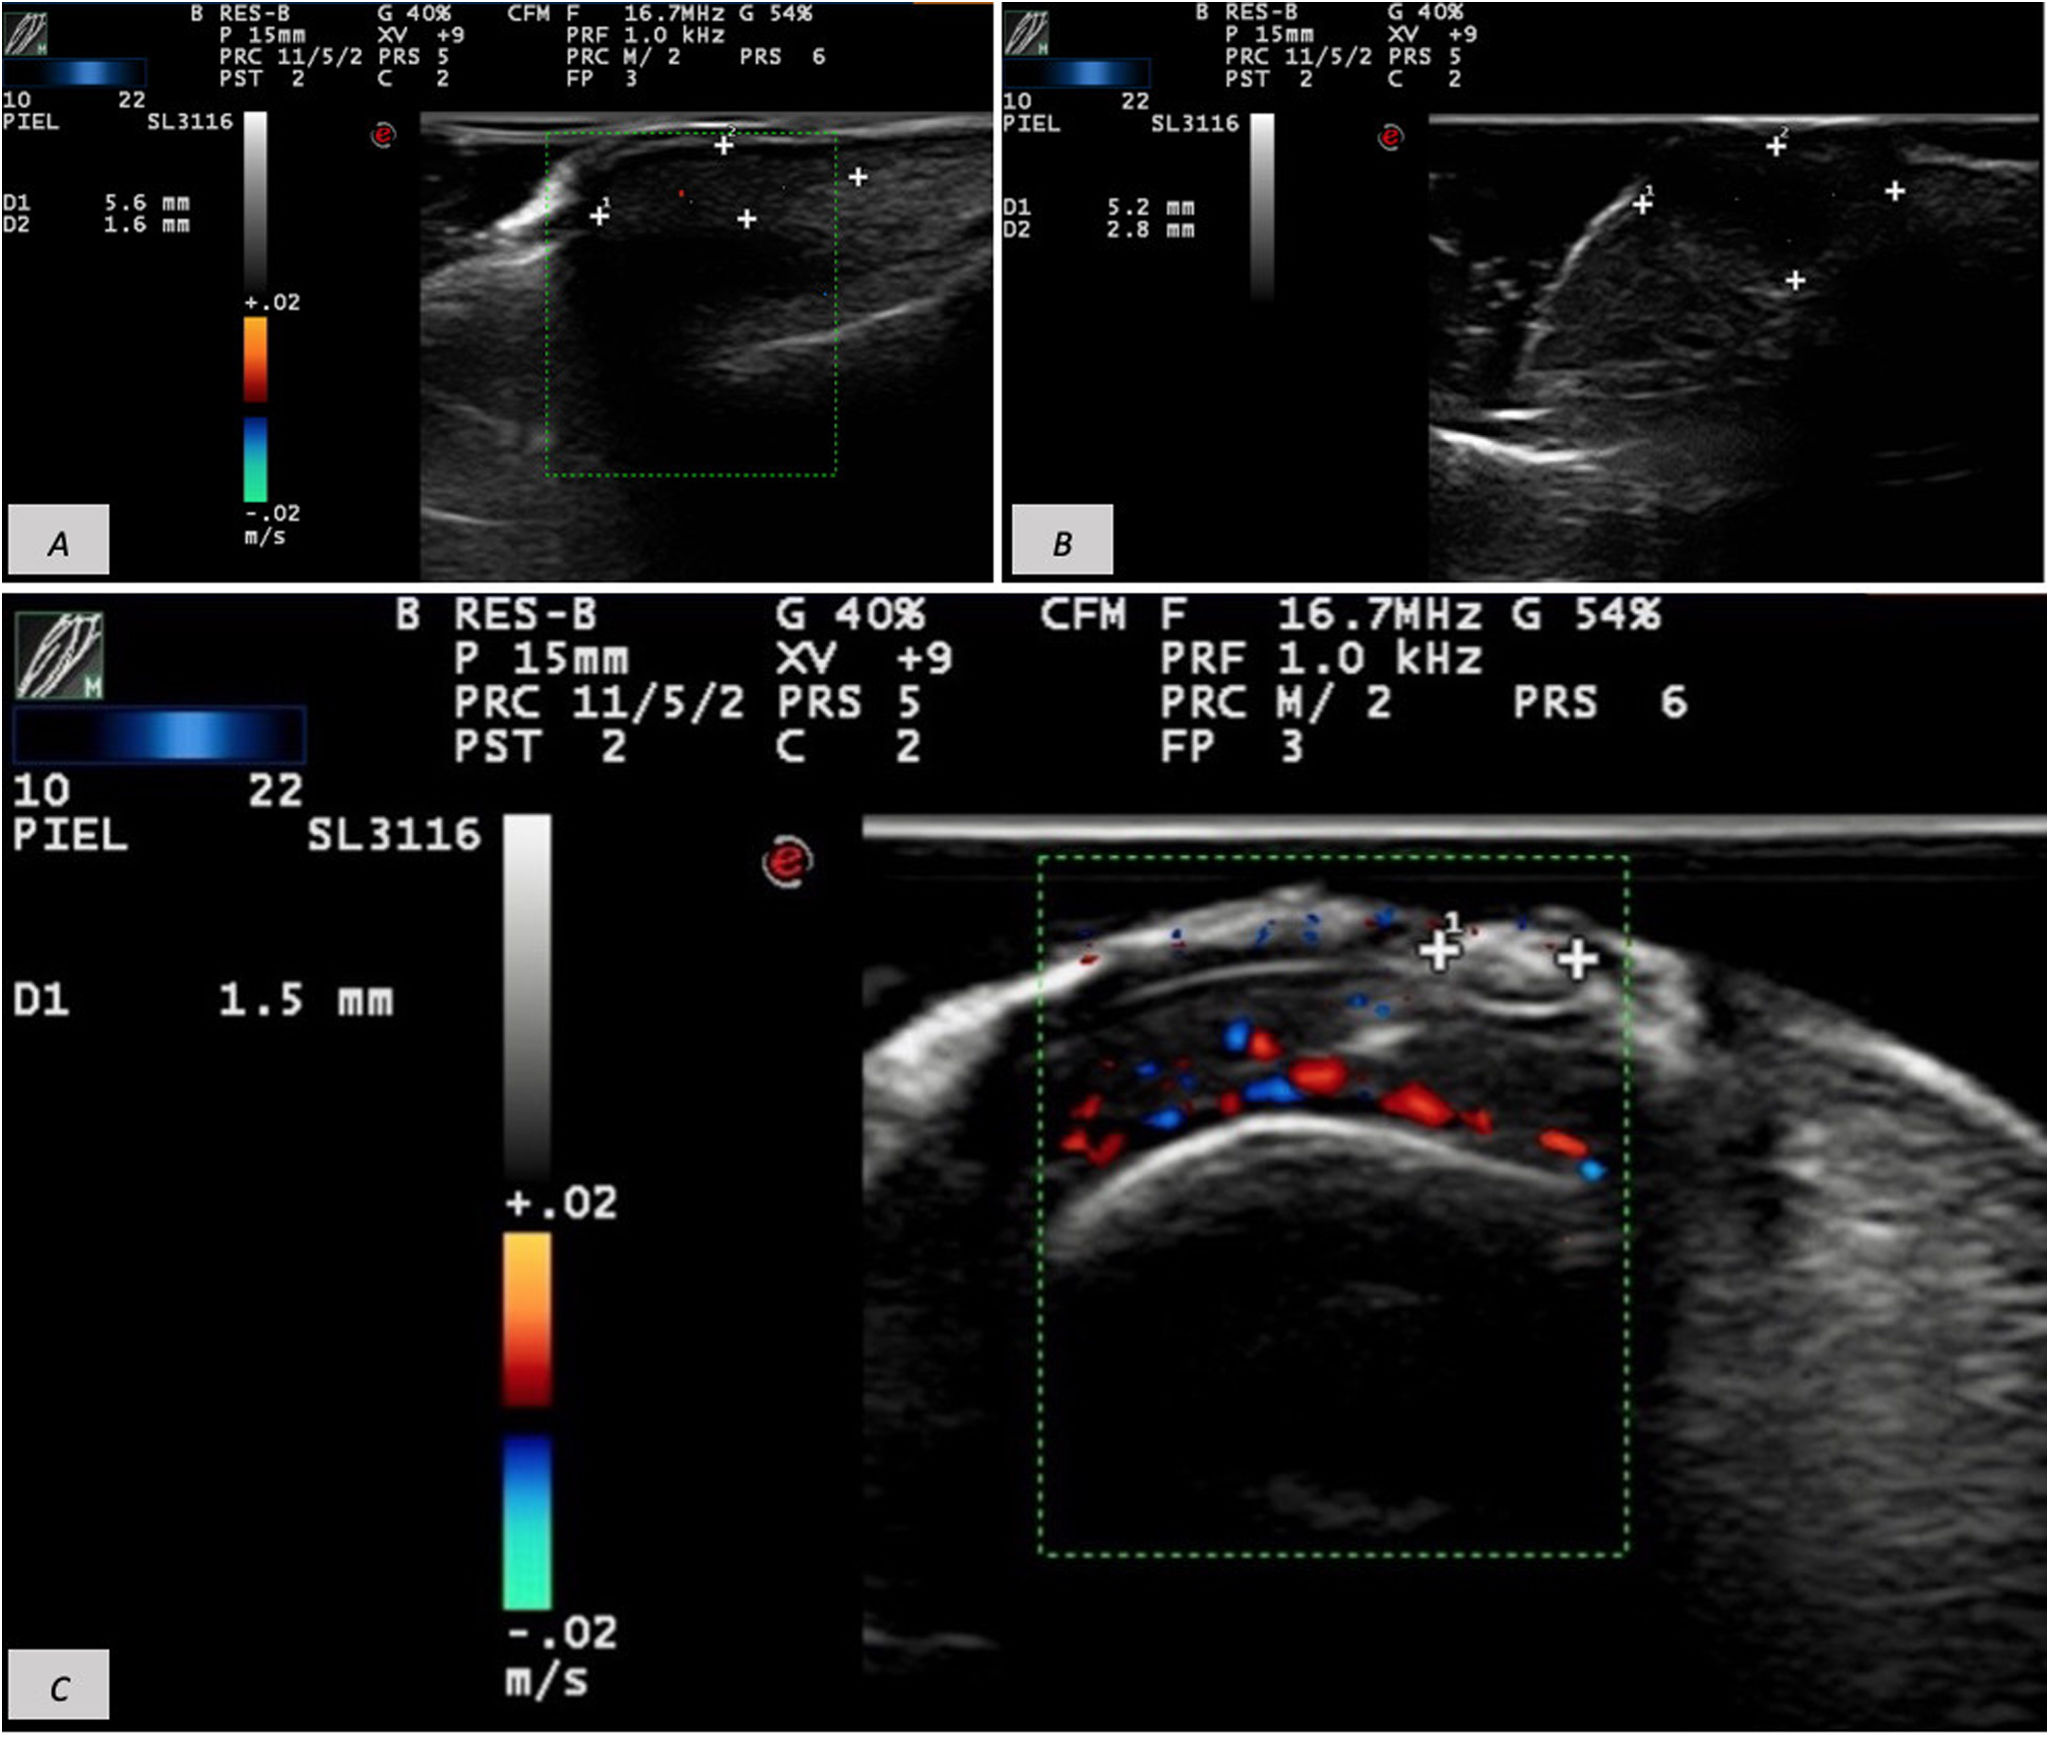

(A) Hypoechoic 5.6mm×1.6mm mass on the proximal nail fold overlying the nail plate without matrix involvement and minimal basal vascularity. (B) Well-defined 5.2mm×2.8mm hypoechoic lesion. (C) Frontal view of a 1.5-mm hyperechoic lesion, unrelated to underlying structures and without Doppler flow.

The 3rd patient was a 37-year-old woman who presented with a 2-year history of a stable, asymptomatic lesion on the 2nd toe of her left foot. Examination showed a 5-mm skin-colored, smooth-surfaced papule lateral to the nail of the 2nd toe, without inflammatory signs. Cutaneous ultrasound was performed with 18-MHz and 22-MHz probes. The 18-MHz probe demonstrated intact bone and nail plate. The 22-MHz probe revealed the presence of a 5.2mm×2.8mm well-defined hypoechoic lesion without Doppler flow (Fig. 2B). As in the previous cases, histopathology after excision confirmed an acquired digital fibrokeratoma.

The final patient was a 55-year-old man with a 5-month history of a lesion adjacent to the supraungual fold of the 2nd finger of his left hand, associated with pain upon contact. Examination showed a crusted, firm lesion of at least 4mm with hyperkeratosis and dystrophic changes, accompanied by a secondary, regular 2-mm gray-brown melanonychia.

Suspecting a subungual wart, dermatologic ultrasound was performed, demonstrating the presence of a 1.7mm×1.5mm soft tissue thickening beneath the proximal fold with no apparent relationship to underlying structures and no Doppler vascular flow (Fig. 2C). Wedge excision was performed, and histopathology revealed an ungual fibrokeratoma.